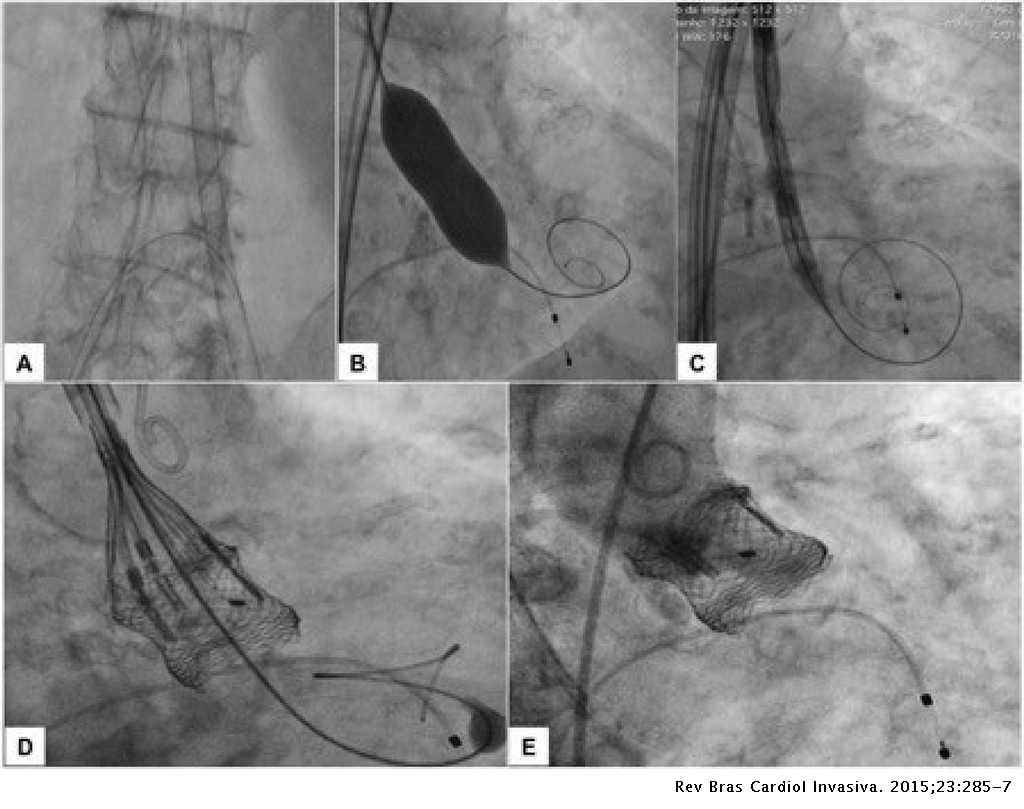

Minimally Invasive Strategy For Transcatheter Implantation Of Second Generation Lotus Aortic Valve System Revista Brasileira De Cardiologia Invasiva English Edition